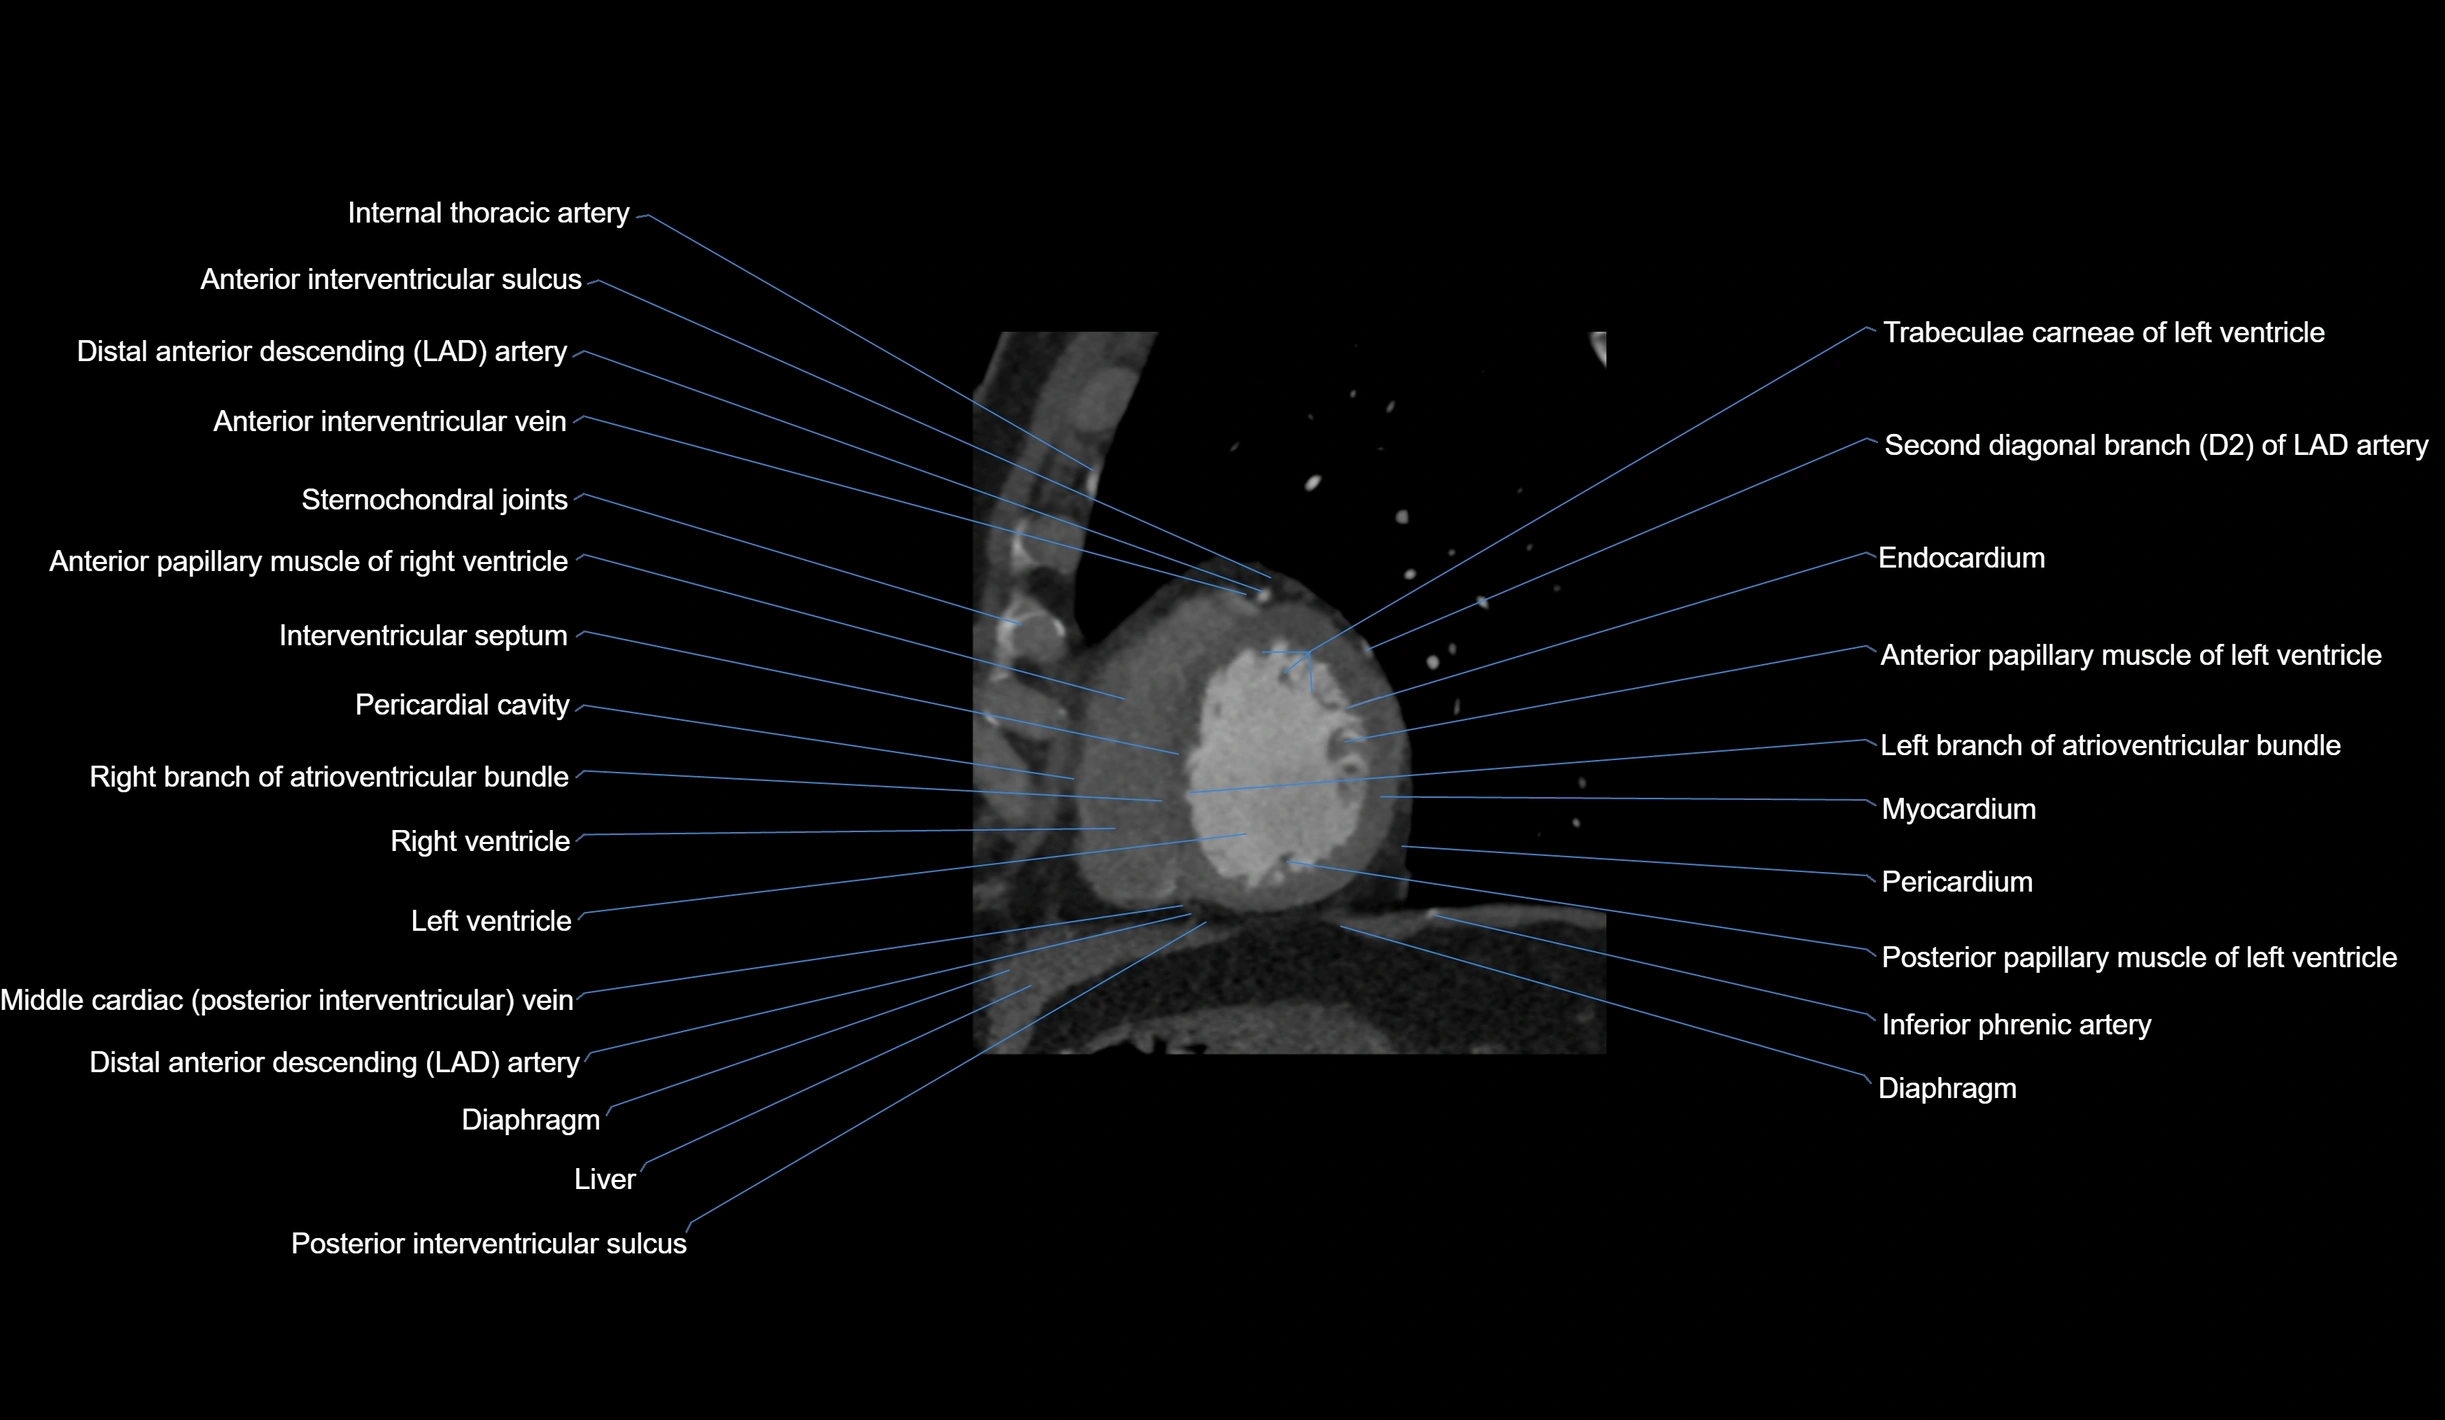

CT images